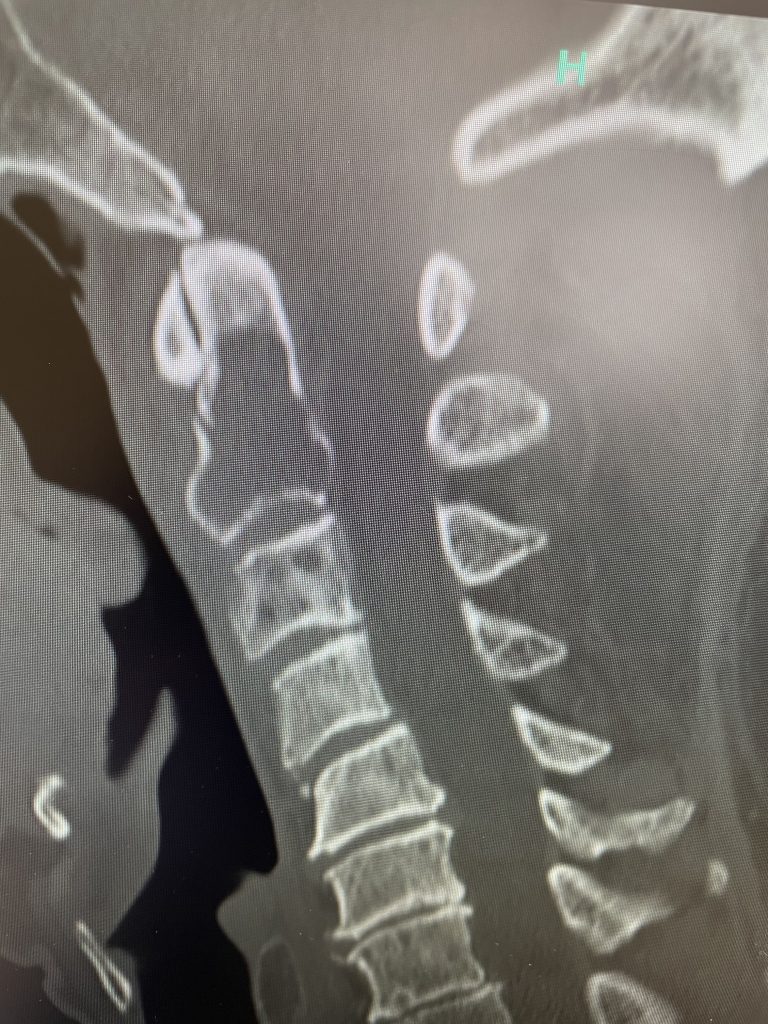

After several months he represented with worsening neck pain and placed in a hard collar. He had a repeat CT scan which showed some progression of disease now more affecting the C3 vertebral body (Fig 11). The patient had flexion extension x-rays which showed stability. The patient was referred to pain management for better control. He was placed in a hard collar. Given the progression of disease after radiation, three columns of the spine affected, progression of neck pain, potential for collapse of the bone and retropulsion into the canal causing quadriplegia, surgical stabilization was offered to the patient. Given the poor bone quality, as one can assume that the multiple myeloma could extend to other adjacent bones, it is challenging to stabilize the patient with good fixation. Options would include stabilizing with hardware and fusion from C1 to C5 which would provide stabilization above and below the area of potential collapse. Another option would be to go from occiput to C5. This is a more morbid procedure and really severely limits head movement. Your “yes” and “no” movements are between your occiput and C2. Most people do not realize that sixty percent of your head and neck motion is between the occiput and C2. The rest is distributed amongst the other cervical vertebrae. If a fusion was carried up to C1, then the patient would not lose as much motion not to mention the significantly increased exposure and risk with an occipital-cervical fusion. The patient declined surgical treatment at this point knowing all the risks. He agreed to wear his collar. He was in better pain control. He will be followed closely.

Fig 2: Sagittal CT scan demonstrating progression of disease into C3 vertebral body